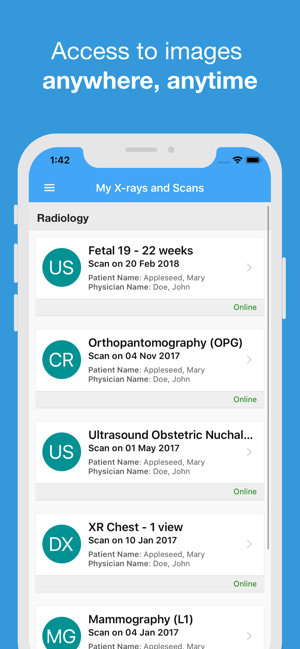

Accessing your images has never been easier with Illawarra Radiology Group.

Use our App any time of the day or night to:

· access your images and reports (after your scan)

· share your results with family, friends or medical professionals

· Request an appointment

· update your email and password

· Manage notifications for your images and your reports